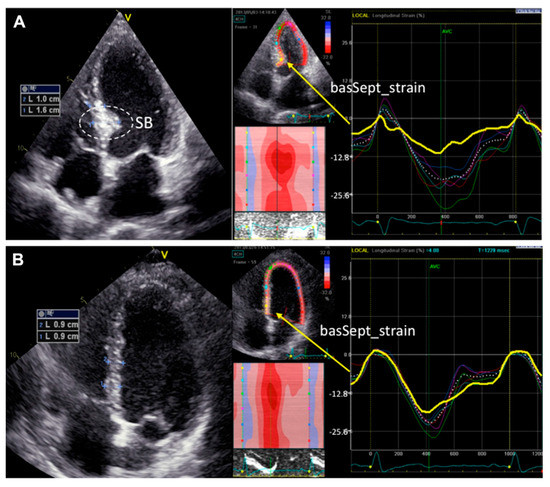

Basal septal hypertrophy (BSH) may be present in approximately 20–25% of patients with hypertension [47] or aortic stenosis [48], and is associated with a decrease in the regional myocardial deformation of the basal-IVS (Figure 2) [49]. In some patients, BSH may increase the risk of dynamic LVOT obstruction even in the absence of underlying hypertrophic obstructive cardiomyopathy [50]. Based on the above, BSH has been proposed as an early imaging biomarker of risk for the progression of hypertensive disease to heart failure [51]. However, the precise definition of the underlying BSH etiology is not always easy, especially in the elderly, where there is overlap between genetic and acquired causes of IVS hypertrophy [52].

Figure 2.

Examples of segmental longitudinal systolic strain curves derived from speckle tracing imaging in patients with (A) or without (B) septal bulge (SB). Gaudron PD, et al. J Am Soc Hypertens 2016; 10: 70–80 [49].